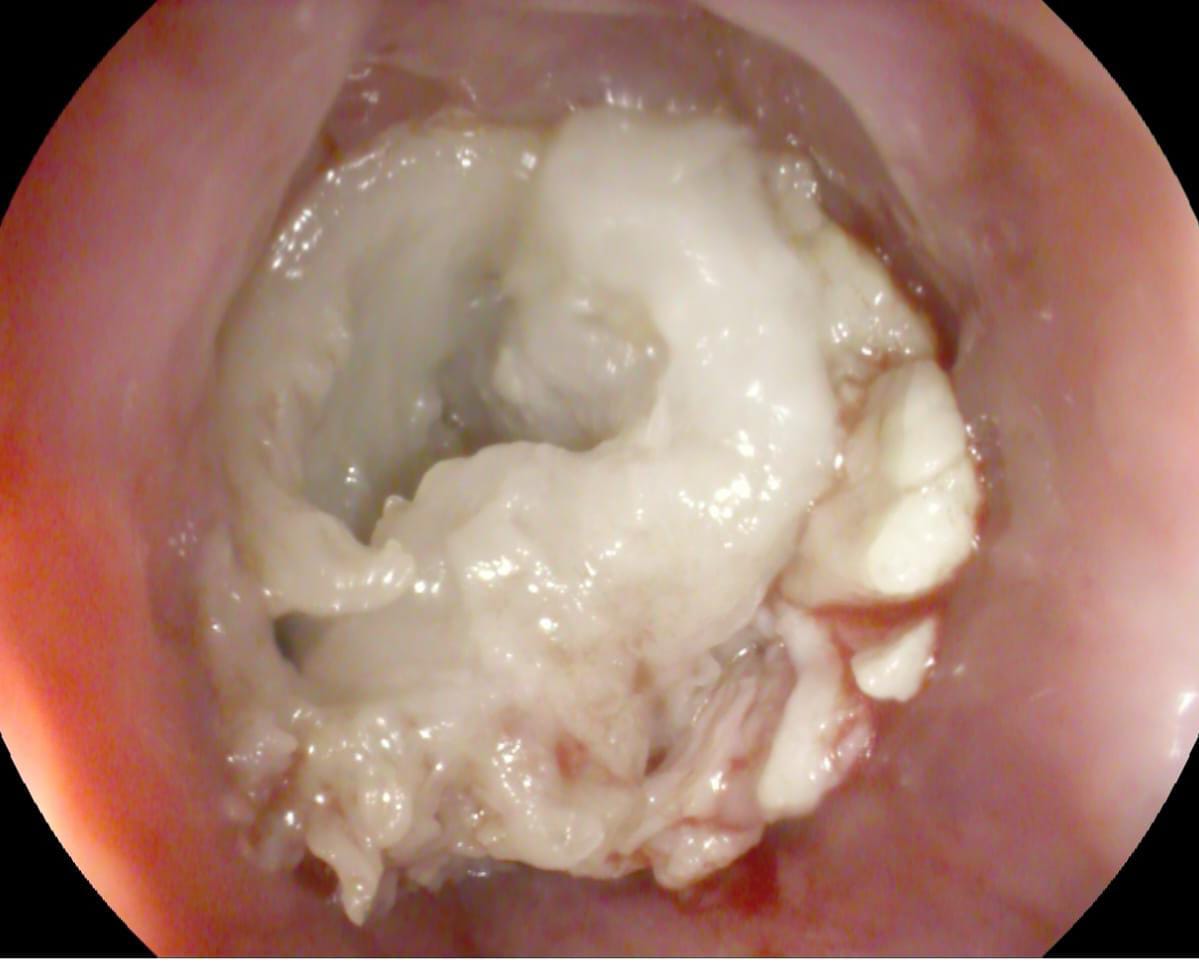

استقبل الفريق الطبي بقسم المناظير بمستشفى أبو كبير المركزي مواطن يبلغ من العمر ٧٠ عامًا، يعاني من صعوبة في البلع؛ نتيجة انسداد مجري الطعام بسبب ابتلاع قطعة لحم كبيرة بداخلها عظمة علقت أسفل صمام المريء العلوي.

على الفور تم استدعاء فريق طوارئ المناظير، وتم عمل منظار معدة تشخيصي طوارئ حيث تم تفتيت قطعة اللحم واستخراج العظمة وأجزاء من قطعة اللحمة، وتحريك المتبقي لتجويف المعدة، وإزاحة الانسداد، كما تم عمل منظار تشخيصي كامل للحالة حتى الإثنى عشر، وبعد الانتهاء من الفحص تبين وجود تحور في نسيج المرئ العلوي، وتم أخذ عينات وإرسالها للتحليل الباثولوجي، وخروج المريض بسلام بعد كتابة العلاج والإرشادات اللازمة له.